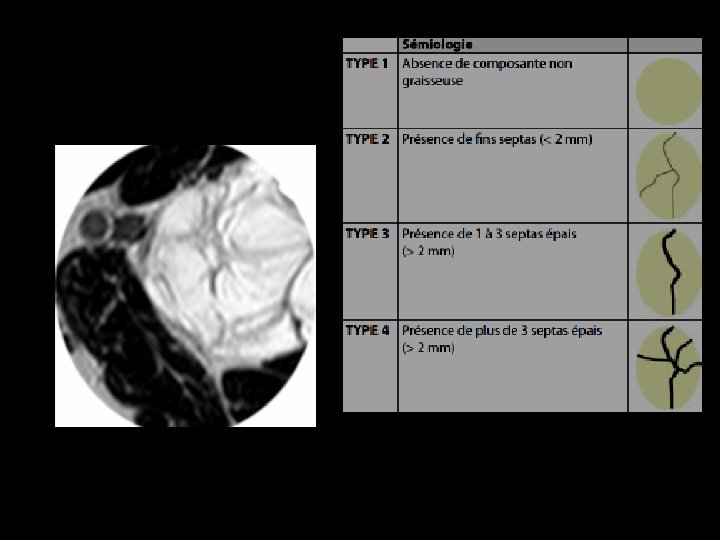

LIPOSARCOME BIEN DIFFERENCIE IRM: • Masse de signal graisseux - en hypersignal T 1 et T 2 - effacement du signal de la graisse • En faveur de la malignité: - septas épais > 2 mm - éléments nodulaires et tissulaires

Liposarcome bien différencié de l’épaule. IRM en coupe axiales en séquences pondérées T 1 (a) et T 1 fat-sat gado (b). Septa épais se rehaussant après injection de Gadolinium contrairement au reste de la tumeur graisseuse

Liposarcome bien différencié de la loge postérieure de la cuisse IRM en coupe axiale (a) et sagittale (b) en séquences pondérées T 1. Volumineuse tumeur de signal graisseux présentant des septa épais et des nodules tissulaires intratumoraux (têtes de flèches).

a Liposarcome bien différencié de la loge postérieure de la cuisse. IRM en coupe axiales en séquences pondérées T 1 (a) et T 1 fat-sat gadolinium (b) La présence d’un volumineux nodule tissulaire intra tumoral se rehaussant de façon important (flèches) est très en faveur de la malignité de la masse. b

Liposarcome bien différencié de la hanche Coupe axiale pondérée SE T 1 (a), frontale pondérée T 2 (b) et axiale pondérée SE T 1 avec Fat Sat et injection de Gadolinium (c): tumeur graisseuse avec des travées nombreuses et relativement épaisses

TUMEURS GRAISSEUSES BENIGNES LIPOME Localisation superficielle Taille < 5 cm Homogène Sépta < 2 mm Pas de nodules MALIGNES LIPOSARCOME BIEN DIFFERENCIE Localisation sous aponévrotique Taille >5 cm Hétérogène Sépta épais Éléments nodulaires et tissulaires